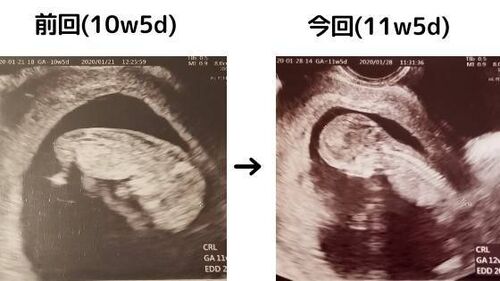

【11w5d】首のむくみ(NT)なくなってた!!0.2ミリ!!!!

こんにちは、ゆーんです 先日は第二子妊娠の報告にあたたかいコメントをありがとうございました。 www.xoyu-nxo.work 大丈夫、おめでとうという言葉にとても支えられました(^^) そして本日。 大丈夫大丈夫…と思いつつも、不安でいっぱいの4回目の検診。 む…